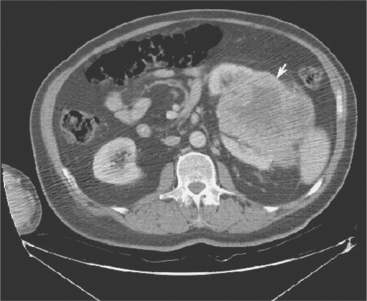

The primary feature of RCC is the renal parenchymal mass, which can be detected by a variety of imaging modalities (Fig. 18-2). The widespread availability of abdominal ultrasound (Fig. 18-3), magnetic resonance imaging (MRI), and CT scanning has increased the diagnosis of incidental renal tumors.

Figure 18-3 Computed tomographic scan of abdomen demonstrating a large left renal mass (arrow) consistent with renal cell carcinoma. (From Townsend CM: Sabiston textbook of surgery, ed 17, Philadelphia, 2004, Saunders.)